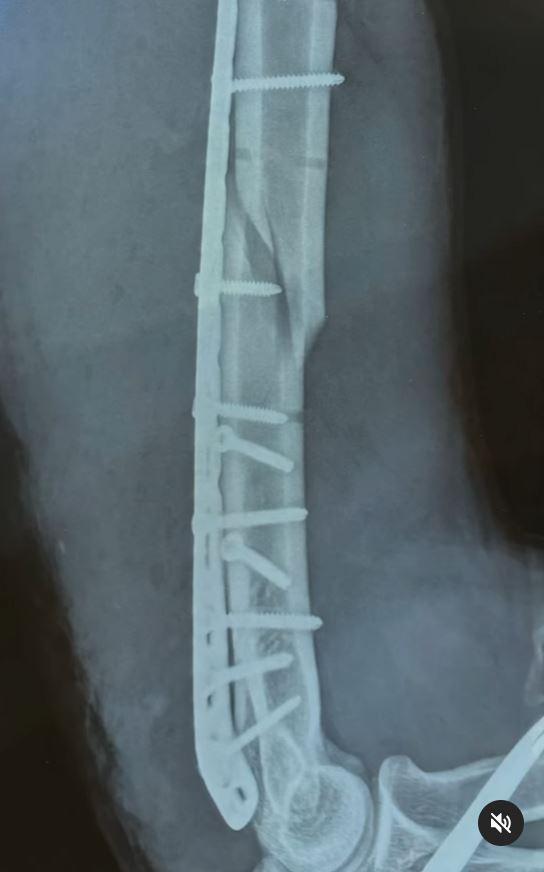

Un difícil momento vive el influencer mexicano Jorge Hernández Ramírez, más conocido en las redes sociales como Sonrixs: El joven sufrió la fractura de su brazo derecho mientras jugaba a las vencidas, conocido como "gallito" en Chile.

El accidente fue tan grave que el joven arriesga perder completamente la movilidad de su brazo derecho: "Nunca imaginé que algo tan cotidiano pudiera tener consecuencias tan graves", dijo.

El problema mayor se dio luego que se rompiera el brazo y fue cuando el hueso fracturado en tres partes, aplastó su nervio radial, el que es fundamental para los movimientos más delicados.

Por lo mismo, debió ser sometido a una cirugía de reconstrucción en donde le pusieron 11 tornillos desde el hombre hasta el codo.

"Mi mano aún no se mueve. Los doctores me dijeron que la movilidad podría regresar o no. Es cuestión de tiempo, y eso es lo más difícil de aceptar", aseguró.